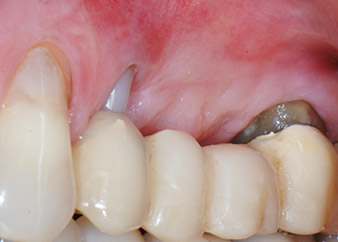

Un mes después, en el día de la intervención, el dolor y la inflamación se habían reducido al mínimo en la pieza 24, pero seguía habiendo una movilidad de clase II de Miller. Después de la apertura de los colgajos y de la limpieza del tejido infectado periapical y perirradicular, la extensión del defecto óseo quedó evidente (figuras 2 y 3).

En la raíz bucal, faltaba todo el hueso vestibular y distal. Básicamente, la fijación se limitó a la raíz palatal, lo que corroboró el mal pronóstico preliminar. La pieza 27 también mostró una fijación horizontal reducida (figura 12) y una rarefacción apical mínima (figura 1), si bien sin síntomas clínicos.

Resultado provisional a los 2 meses

Las figuras 17 y 18 muestran el resultado clínico 2 meses después de la intervención quirúrgica. La pieza 24 tenía una movilidad reducida clase I de Miller y los tejidos blandos no presentaban inflamación. Se evitó el uso de una sonda en este momento para evitar una nueva infección y para no romper la fijación epitelial. El siguiente control se planificó para el momento en el que se reanudara el tratamiento y se colocaran los pilares de cicatrización, 6 meses después de la inserción de los implantes.